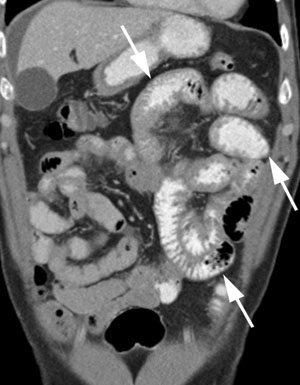

Ny gastroskopi etter innkomst viste noe ødematøse slimhinner i duodenum som gjorde det noe vanskelig å intubere pars descendens duodeni med endoskopet, ellers var det ingen patologiske forhold. CT abdomen/bekken (fig 1) viste noe ascites og prepylort var ventrikkelveggen sirkulært og diffust lett fortykket. Horisontale del av duodenum samt jejunum hadde noe uryddig slimhinnerelieff med fortykkede folder og fortykket tarmvegg som var litt uskarpt avgrenset mot fettvevet. Det var lett markerte lymfeknuter i jejunumkrøset. På overgangen til ileum ble tarmslyngene normalisert. Fecesprøver med tanke på patogene tarmbakterier, parasitter og kalprotektin var alle negative. Han var også Helicobacter pylori-negativ.

Det er uavklart hvor stor andel av pasientene med eosinofil gastroenteritt som har radiologiske forandringer. Tilstanden har ikke patognomoniske forandringer ved bildediagnostiske undersøkelser, funn er både uspesifikke og variable, men minner mer om inflammatorisk affeksjon enn neoplastisk sykdom. De vanligste funnene, vesentlig ved mukøs affeksjon, er fortykket tarmvegg og uregelmessig tarmrelieff med fortykkede irregulære folder. Ved affeksjon av dypere vegglag kan man se rigiditet, dysmotilitet og stenose. Ved subserosal affeksjon kan man finne ascites, ødematøst fettvev, adheranser og forstørrede lymfeknuter (21, 22). Enkelte tilfeller av perforert tarm er også publisert (15).

Man kan finne uspesifikke forandringer ved en rekke bildediagnostiske undersøkelser som oversikt abdomen, ultralyd abdomen og tynntarmspassasje, men CT abdomen vil gi mest spesifikk diagnostisk informasjon. Etter vår erfaring gir CT utført med kontrastmarkert tarmlumen og intravenøs kontrast de beste muligheter for å oppdage tilstanden. Radiologisk er det mange differensialdiagnoser, men det er viktig å være oppmerksom på denne type uspesifikk tarmpatologisk tilstand og mulighet for eosinofil gastroenteritt.